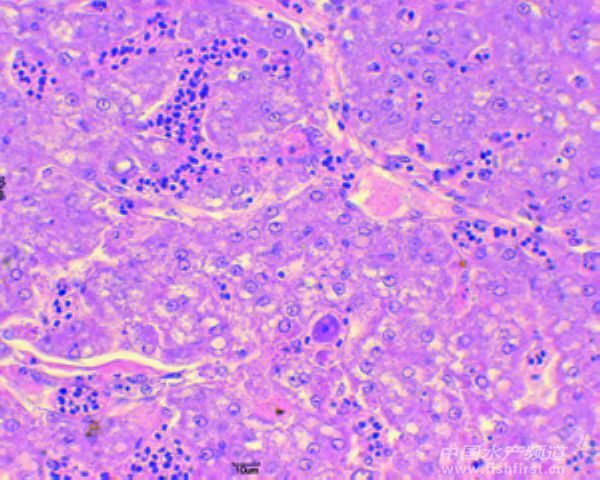

圖9 肝臟淤血,肝細胞界限不明,肝實質細胞稀疏,有零星肥大細胞,有壞死